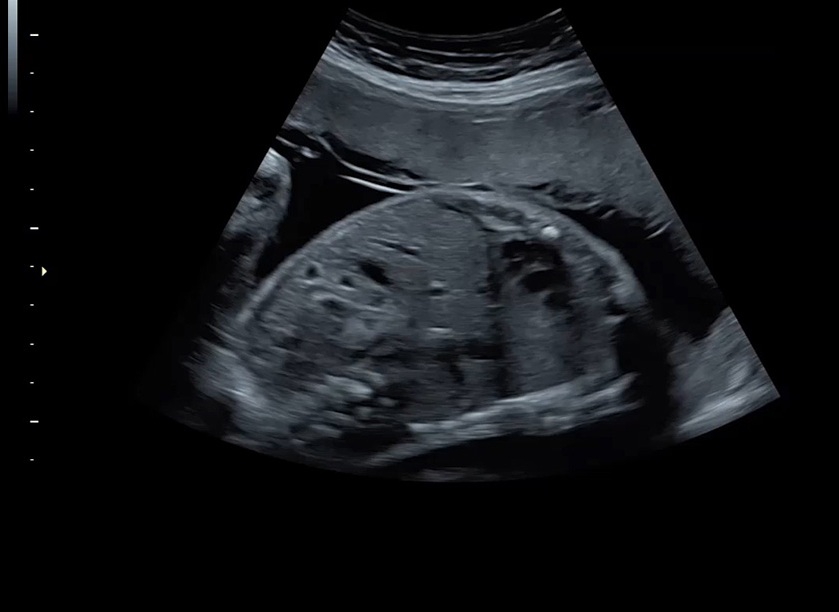

Ультразвуковая платформа Voluson S8 представляет собой оборудование экспертного класса с передовыми возможностями и высоким уровнем автоматизации процессов. Она позволяет проводить сканирование в режимах 2D, 3D и 4D с высоким качеством изображений.

Аппарат Voluson S8 базируется на надежной платформе VCA, которая имеет множество положительных отзывов. Она обладает высококонтрастной технологией объемной реконструкции, обеспечивая качественное воспроизведение изображений. Информация выводится на широкоформатный цветной монитор размером 23 дюйма для убедительной демонстрации плода будущим родителям и облегчения работы врача.

• Высокое качество изображений: Voluson S8 обеспечивает высококачественные изображения, позволяющие детально оценить состояние плода и обнаружить возможные патологии.

• Высокочувствительные датчики: Ультразвуковой сканер Voluson S8 оснащен высокочувствительными датчиками, что позволяет проводить полноценное обследование даже у пациентов с сложными анатомическими особенностями.